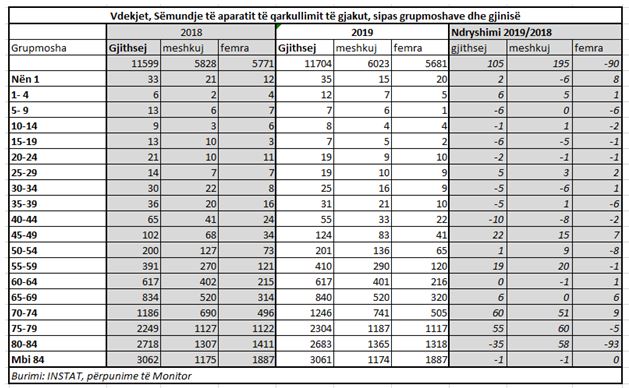

Rritja ka ardhur tërësisht nga meshkujt, humbjet e jetëve të së cilëve janë rritur me 3.2%.

Meshkujt përbëjnë dhe përqindjen më të lartë të humbjes së jetëve nga kjo sëmundje, me 51.5%, përkundjet 50% të grave. Për 1,000 banorë, grupi i sëmundjeve të “aparatit të qarkullimit të gjakut” është shkaku kryesor i vdekjeve si tek burrat dhe tek gratë me një nivel vdekshmërie 4.2 për burrat dhe 3.97 për gratë (për shkak të numrit më të lartë të grave në total, teksa 50.8% e popullsisë në total ishin femra në 2019-n).

Në vitin 2019 është konstatuar një rritje e lartë e vdekshmërisë nga zemra dhe tensioni në grupmoshën e meshkujve 45-49 vjeç (+17%) dhe 55-59 vjeç (+4.6%)

46% e vdekjeve të meshkujve nga kjo sëmundje ishin të grupmoshës nga 40-59 vjeç, kundrejt 43% që ishte një vit më parë.